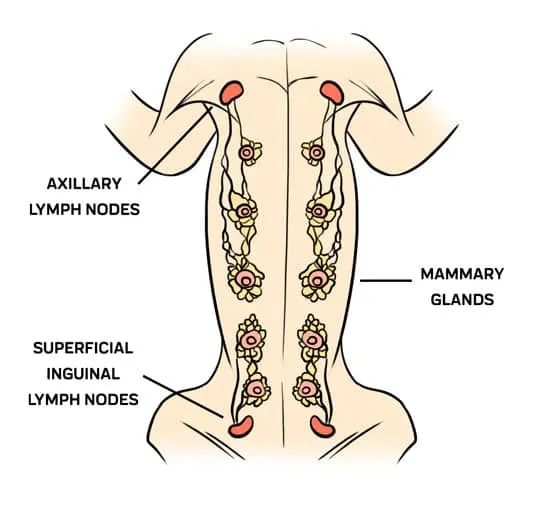

3.可能是需要用最大範圍去切除的小型腫瘤 :因為其多發的特性還有高的淋巴轉移機率,標準做法是整排乳腺切除或者至少要切除共用淋巴收集區的其他乳腺!

:因為其多發的特性還有高的淋巴轉移機率,標準做法是整排乳腺切除或者至少要切除共用淋巴收集區的其他乳腺!

3.可能是需要用最大範圍去切除的小型腫瘤